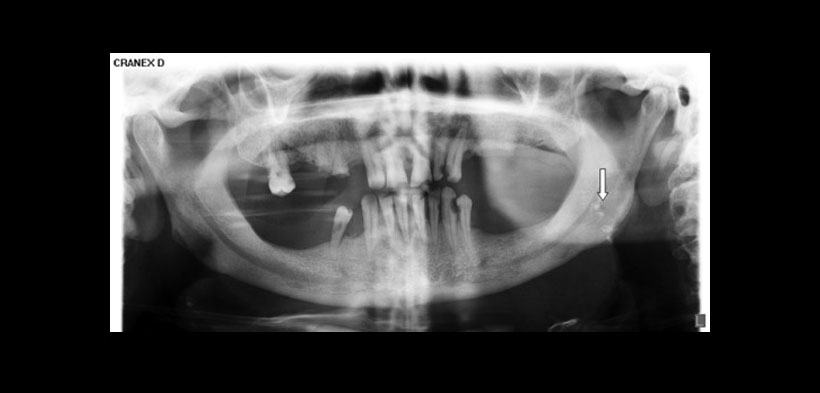

Las radiografías son la primera herramienta de diagnóstico para detectar estas calcificaciones. En las radiografías panorámicas, la amigdalitis y la presencia de los tonsilolitos aparecen como radiopacidades bien definidas simples o múltiples localizada en la rama de la mandíbula, en la región donde la superficie dorsal de la lengua atraviesa la rama con el espacio de aire glosofaríngeo. Aunque estas radiopacidades se ven generalmente en un área limitada (amígdala palatina), pueden ser mal diagnosticados con otras lesiones calcificadas en la imagen. Así, tonsilolitos deben ser considerados como el primer diagnóstico diferencial de múltiples radiopacidades mal definidos detectados en la úvula palatina y rama. Los tonsilolitos se pueden encontrar superficialmente en las criptas amigdalinas, visto como una masa calcificada amarillento o más profundamente localizada como una lesión dura ampliada.

Fig. 1. Un caso de tonsilolitos bilaterales acompañado unilateral de la calcificación de la apófisis estiloides del lado derecho.

Fig. 2. Múltiples imágenes radiopacas compatibles a tonsilolitos en la región amigdalina del lado izquierdo.